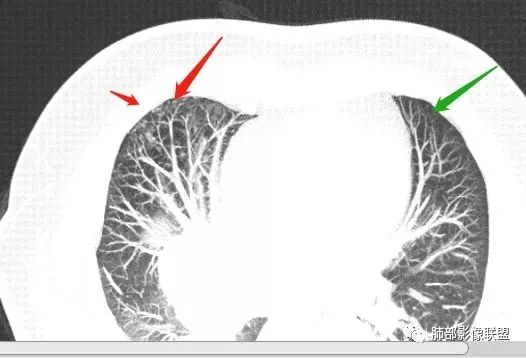

局限性中央间质增厚,考虑癌性淋巴管炎

部分区域有结节感

Coke with ice: 这个是标记的结节感吗?

南边: 奇怪,你们都不觉得这里有结节?

了: 气腔结节

毛勤香: 这个人有癌淋,有点结节感

Coke with ice: 嗯,不明显的结节感可以考虑用MPR和薄层结合起来看,会不会判断的更准一些

2.右肺小叶间隔增厚伴微小结节,提示癌性淋巴管炎。